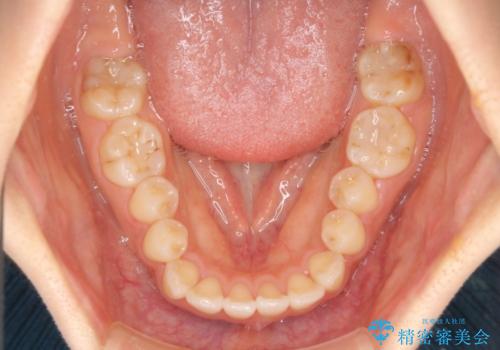

- 飛び出した前歯と口元の突出感を気にして来院された患者様です。

奥歯の咬み合わせを見ると、上顎が下顎に対して相対的に前方にありました。

口元の突出感を改善するためには、上顎臼歯を後方に移動させた咬み合わせにする必要があります。

インビザライン単体で改善することも可能ですが、達成する可能性が高くないため、カリエールディスタライザーという補助装置を併用して、より確実性を上げることとしました。

奥歯の咬み合わせを改善しながら、並行してインビザラインで歯列を整えることとしました。

カリエールディスタライザーを併用したことで、確実かつ短期間で治療を終えることができました。